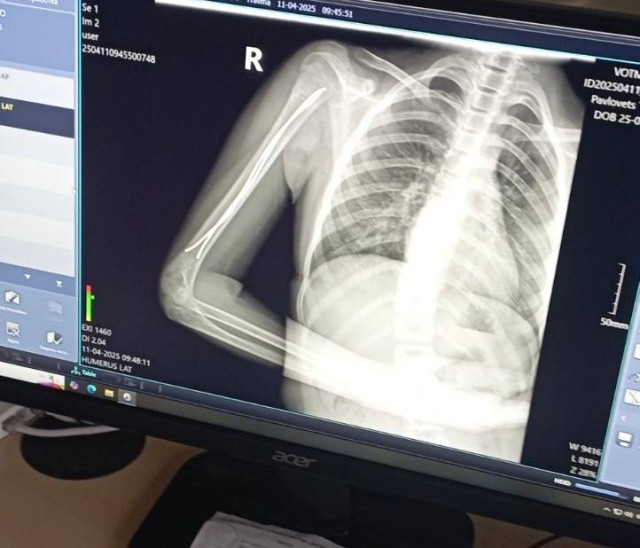

Дворічний Даніель отримав важку травму вдома – бігав, упав. Як наслідок – косий перелом стегнової кістки, складний для вправлення та лікування, утримання відламків.Ортопед-траматолог Ігор Тарасюк пояснює: «Лікування гіпсовими пов’язками хлопчику не підходить, тож раніше діти з такими травмами лікувалися впродовж місяця на витяжінні, а після цього застосовували кокситну гіпсову пов’язку, яка утруднювала рухи. Завдяки внутрішньокістковій фіксації еластичними титановими стержнями дитину виписуємо додому вже наступного дня. Хлопчик, хоч і з певними обмеженнями, але вже може самостійно рухатися».Ще одна пацієнтка відділення — 11-річна футболістка Юля, яка невдало впала на плече під час гри. Як наслідок – перелом плечової кістки зі зміщенням. Раніше через такий перелом довелося б носити велику гіпсову пов’язку на руці – від кисті до плеча, також гіпс накладали б для фіксації і на обидва плеча.Після операції через два-три дні дівчинка вже вільно рухає рукою, не відчуває обмежень. На руці залишиться лише невеликий шрам у 2-3 сантиметри. Через кілька тижнів дівчинка зможе повернутися до занять футболом.Читати ще: Арахіс у легенях, магніти в стравоході та опіки від побутової хімії: волинські лікарі розповіли, із чим до них привозять маленьких пацієнтів